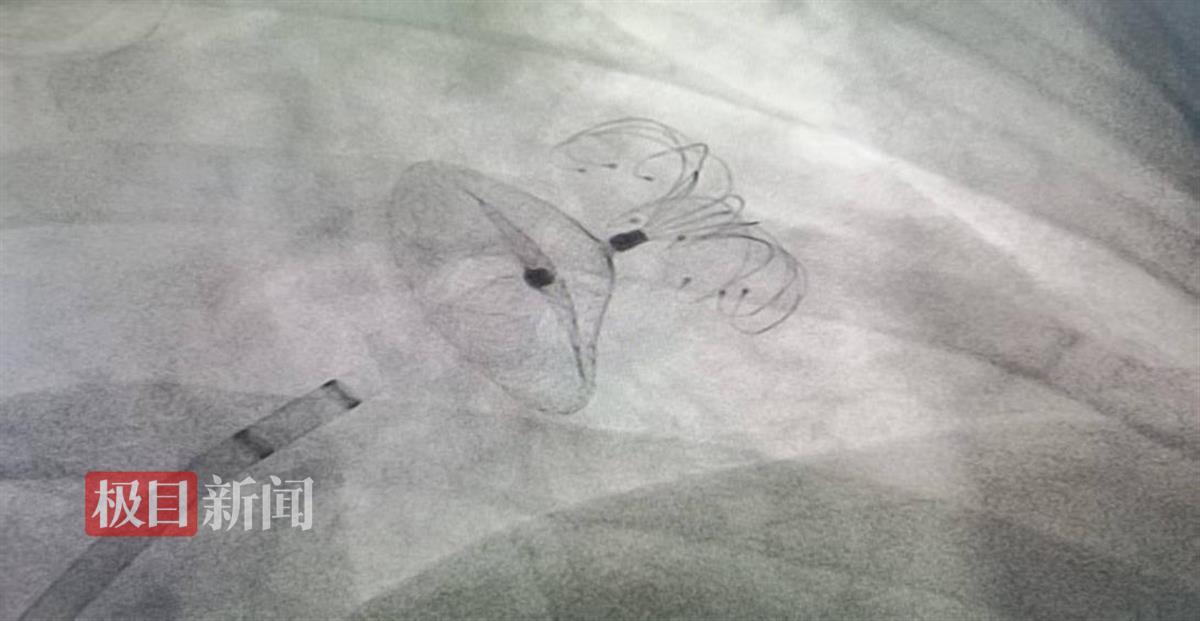

一枚直径34毫米的“伞状”封堵器,40分钟化解致命危机。日前,湖北十堰市太和医院成功为反复脑卒中的高危房颤患者实施左心耳封堵术,拆除这颗引发中风的“炸弹”。

手术面临特殊挑战:患者心脏存在罕见的大尺寸房间隔膨出瘤,穿刺难度倍增。医院特邀武汉大学人民医院黄鹤教授现场指导,结构性心脏病团队精密配合,仅用40分钟完成封堵。术后患者次日即可下床,两天后康复出院。